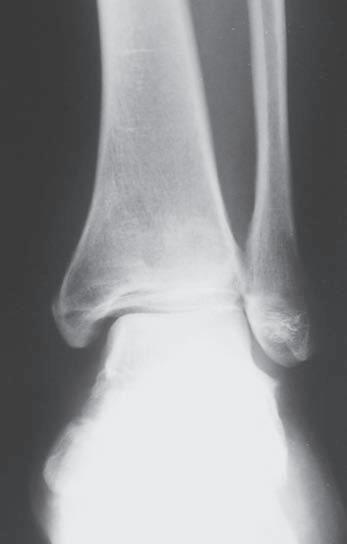

Obr. 1.4 Skiagram hlezna v předozadní projekci – normální fyzární linie na distální tibii a fibule (viz šipky) u adolescenta